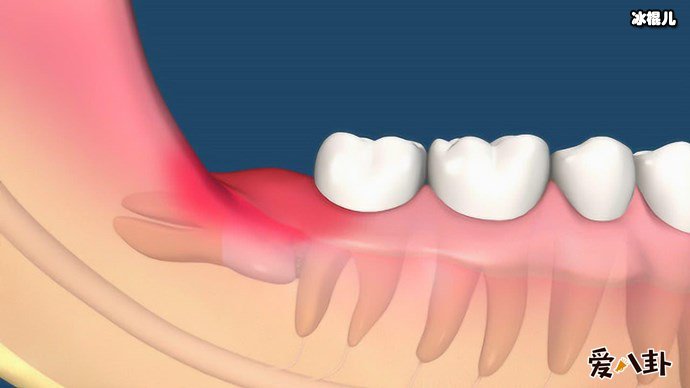

众所周知,人类已知的无法阻止的痛中,长智齿这个疼也是要命,虽然长智齿痛不要命,但是痛起来要命!不知道在座的各位网友有没有经历过这种痛呢?那么这个长智齿又该怎么去缓解或者根治呢?让我们一起来了解了解吧!

说到智齿也就是人们说的智慧齿,智齿实际上是口腔中的第三大臼齿(一般人都有第一和第二大臼齿),因为张智齿的年龄大都是在刚成年的时候,有了智慧所以俗称智慧齿,一般来说有四只智慧齿分别形成始于上下颚骨中,智齿跟其他牙齿一样,但是智齿很不一样的是智齿是最后长出的臼齿,一般智慧齿成形成于9岁而齿冠则于大约14岁形成,并在青春期末长出于口腔中。

不少人都被智齿折磨的痛不欲生,所以么长智齿疼又应该怎么办呢,有这么一个小窍门,如果疼的时候可以含点冰块缓解疼痛,或者用冰块在脸部外敷,一般平时在饮食上要注意,吃的太辛辣就会加重疼痛感,而且每天都要注意清洗口腔,避免口腔滋生细菌,导致长智齿的部位发生感染,一般来说长智齿了就应该马上去医院处理拔掉它,不然智齿压迫了神经,不处理就会遭受长期的疼痛折磨还有进一步加重